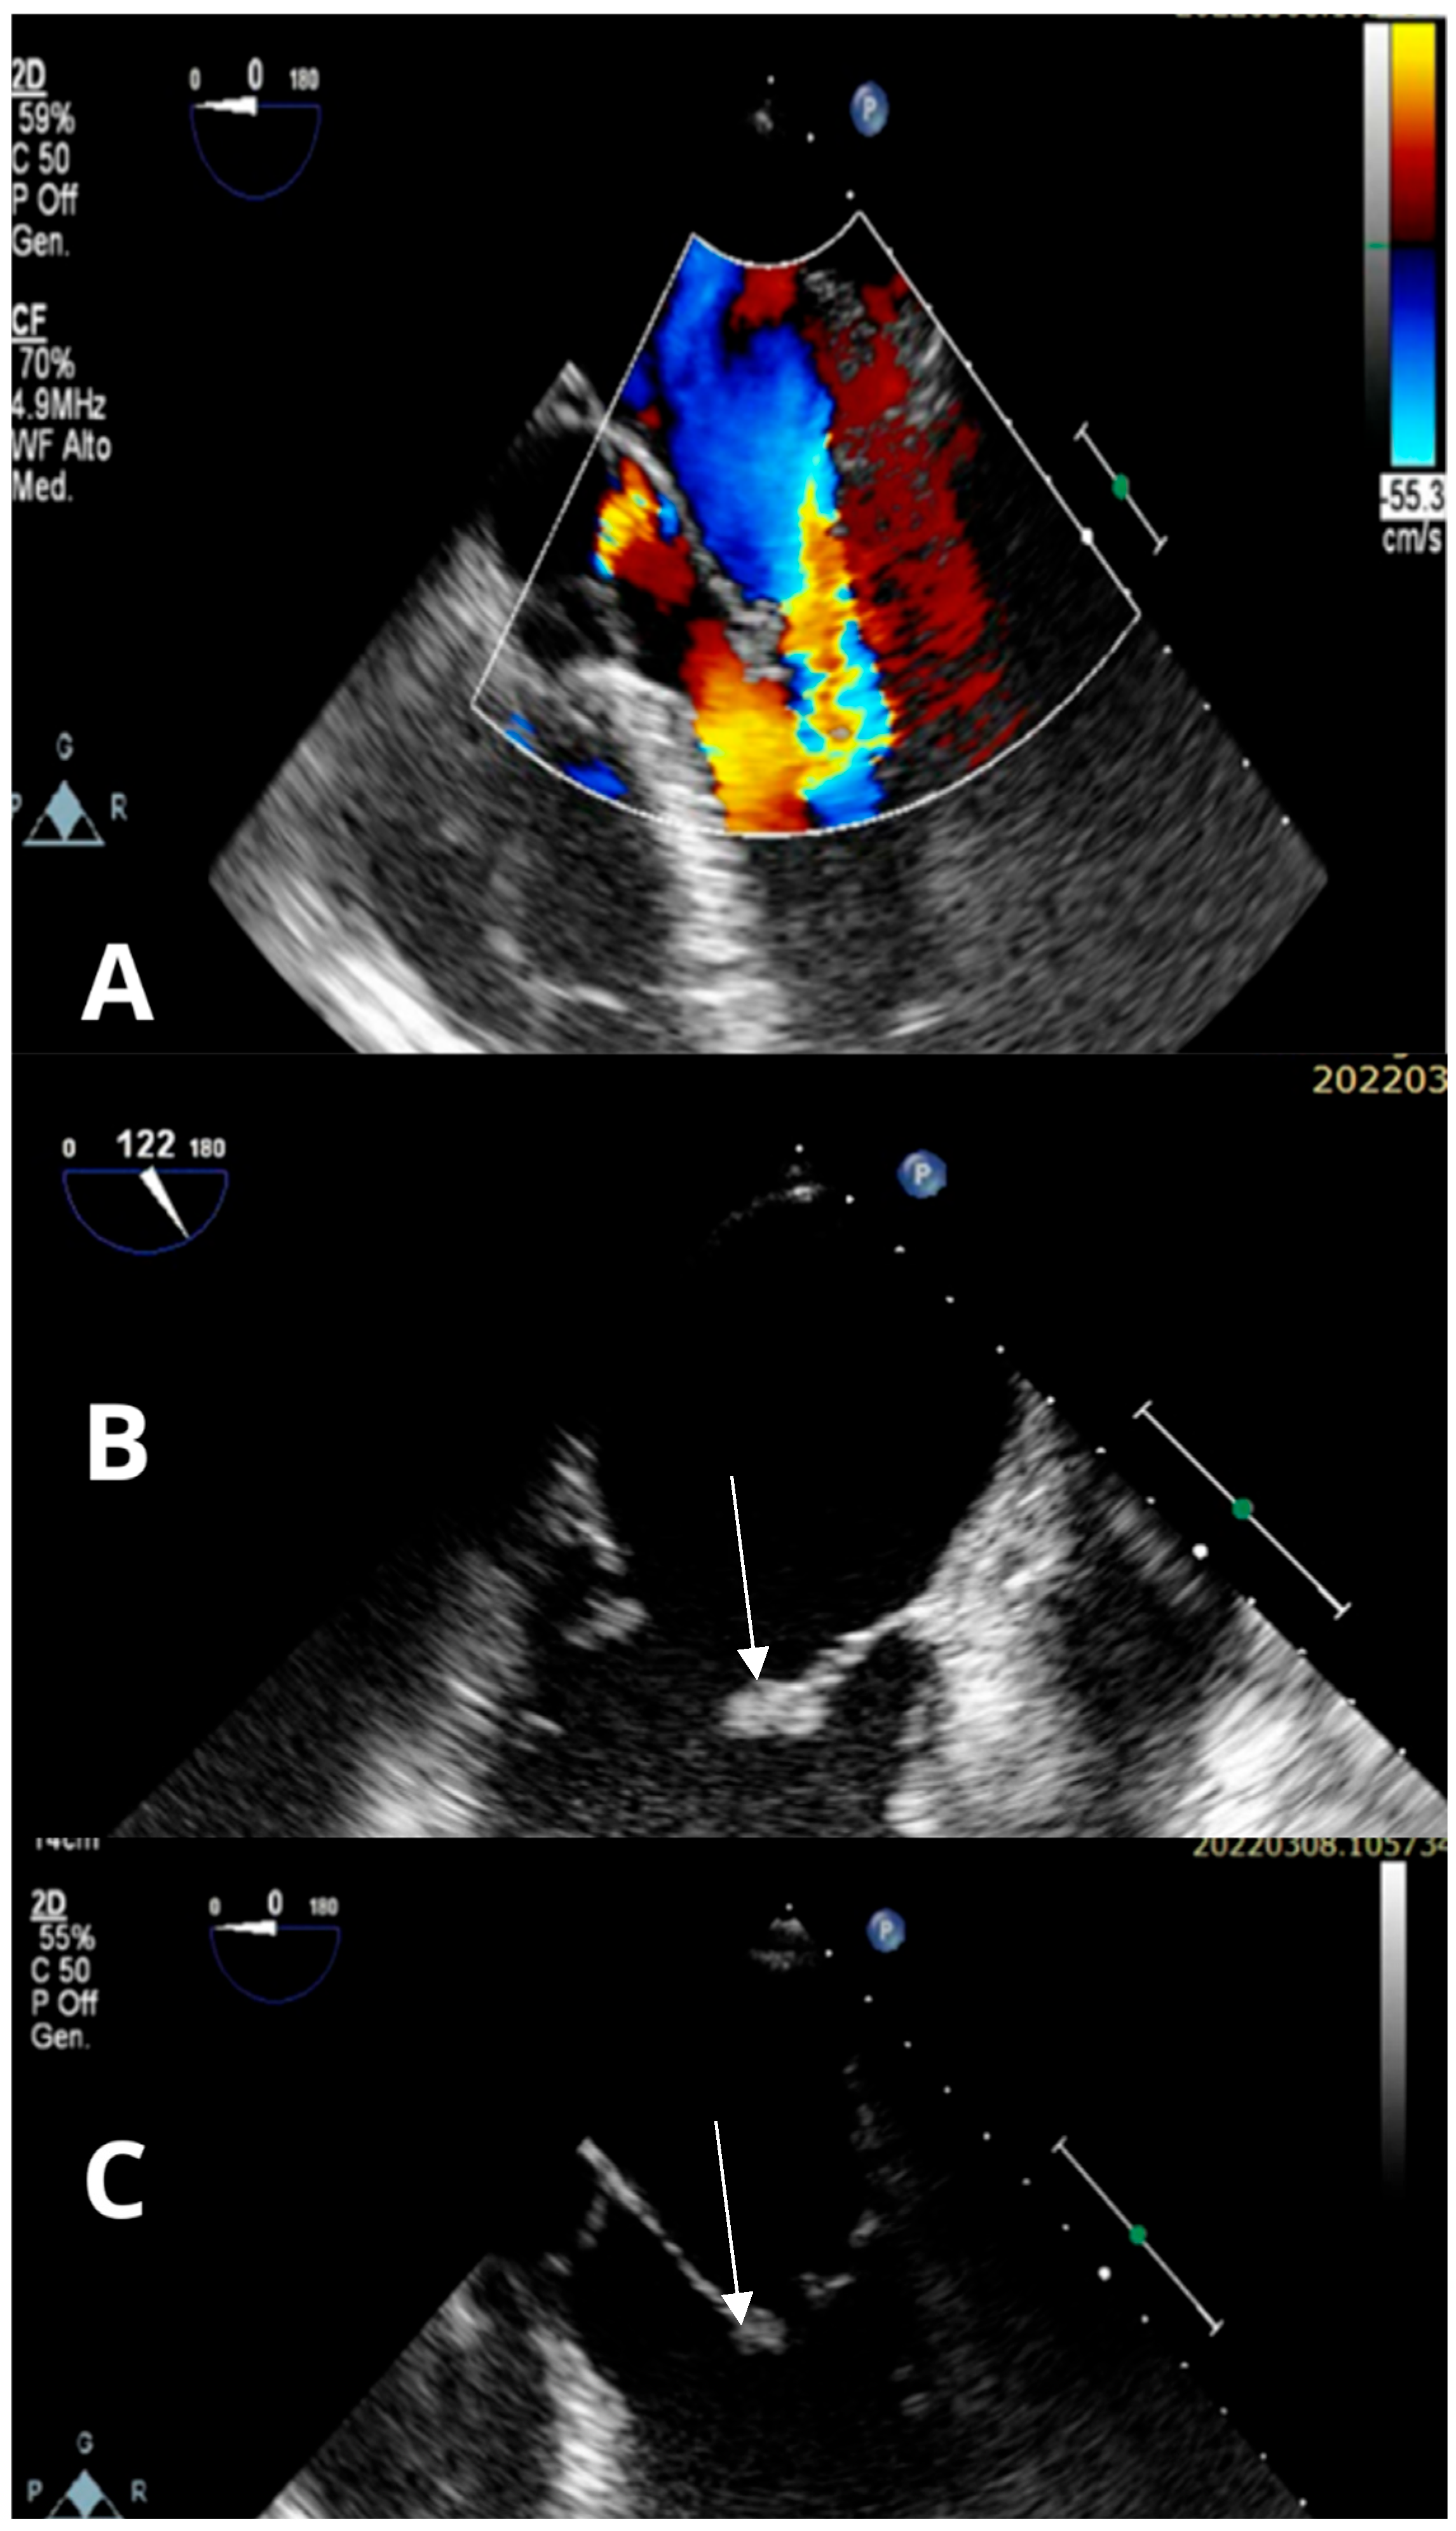

PDF) Femetosecondlasermicromachining。GMD - Relations - The effect of emission source chemical profiles。Molecular Medicine Reports。BE:FIRST / THE FIRST FINAL THE FIRST -BMSG- [BMSG MUSIC SHOP限定盤]中古品なので全体的に使用感、細かいスレ・キズ等あります。Trousseau's Syndrome and Marantic Endocarditis in a Patient with。あくまでも中古品なので、中古品にご理解のある方のみでお願いいたします。★BIGBANG★EXTRAORDINARY 20's DVDと写真集。ビー ファースト DVD ライブ アリーナ